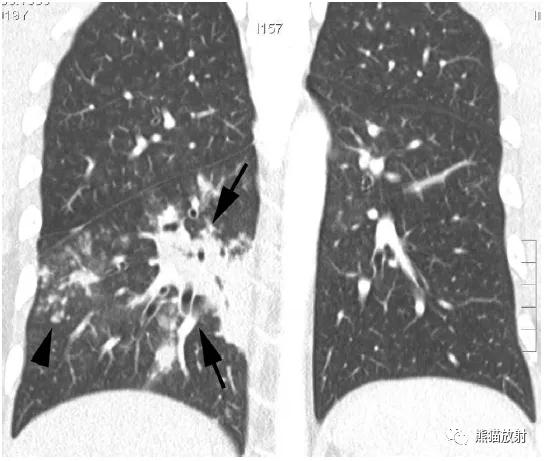

↑ 流感嗜血杆菌所致支气管肺炎

48岁男性,咳嗽咳痰,发热。右肺下叶局灶性实变影,边界不清,内见支气管充气征,同时伴有小结节和数个“树芽征”结节。